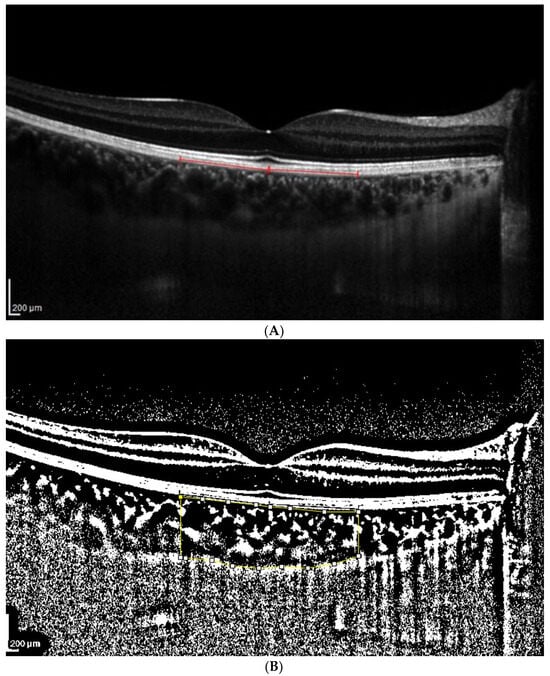

Figure 1.

(A). Patient 1 EDI-OCT right eye scan at 8 level brightness. Red line indicates the RPE. (B). Patient 1 EDI-OCT binarized right eye scan at brightness 8. Assessment of total choroidal area. (C). Patient 1 EDI-OCT binary right eye scan at 8 brightness. Assessment of luminal choroidal area and stromal choroidal area. Yellow lines highlight the yellow choroidal area being calculated.